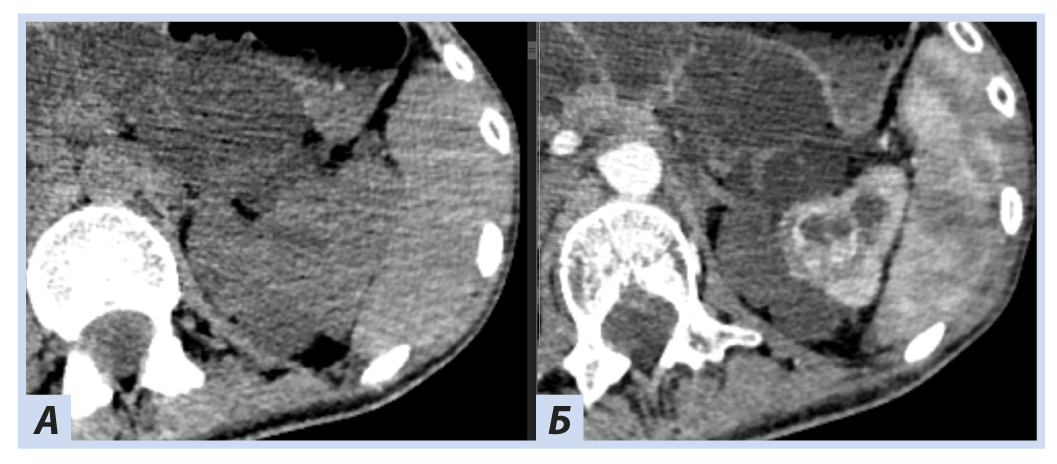

Рис. 2. Пациентка П., 30 лет, с диагнозом «Болезнь Гиппеля−Линдау»: компьютерная томография головного мозга

Примечание. Отмечаются гиперденсные зоны в области сетчатки и глазных яблок справа плотностью до +270…+330 HU.

При скрининговом ультразвуковом исследовании забрюшинного пространства были выявлены изменения обеих почек, которые были интерпретированы как множественные кисты при дообследовании на КТ забрюшинного пространства: множественные кистозные образования обеих почек; в верхнем полюсе левой почки — кистозно-солидное образование, изоденсное паренхиме почки в нативную фазу (40 HU), в артериальную активно накапливающее контраст (до 100 HU), контуры его четкие неровные (рис. 5, 6).

Рис. 5. Пациентка П., 30 лет, с диагнозом «Болезнь Гиппеля−Линдау»: компьютерная томография забрюшинного пространства

Примечание. А — нативная фаза: кисты обеих почек, солидный узел в верхнем полюсе левой почки; Б — артериальная фаза: кисты обеих почек более отчетливы на фоне контрастированной почечной ткани, солидный узел в верхнем полюсе левой почки с неоднородным накоплением контраста опухолью.